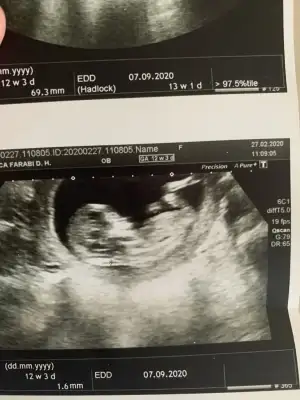

dr soylemeden siz gorun genital nub teorisi ( bebegin cinsiyeti)

Senin nubu çizdim cnm arkadaşında çizdim pipide vardı arkadaş pipi olsa söylemezmi deyince bende diğer 10 ve 11 haftasndaki tahminim devam dedim çok istiyordu pipiyi dr görmedi deyince ne kadar geç ögrenise dedim yoksa baya baya pipiydi çizdiğim usg 😊 seninkinide çizdim parelel görünüyor tabi pozisyonu nubu bazen değiştiyor. umarım 31 yanlış tahminim var arasında olmazsın onlar beni yanıtan usgler 😊

teşekkürler doktor erkek gibi ama emin değilim dedi 1 ay sonra kontrol inş. geri dönüş yapacağım iyi akşamlar.